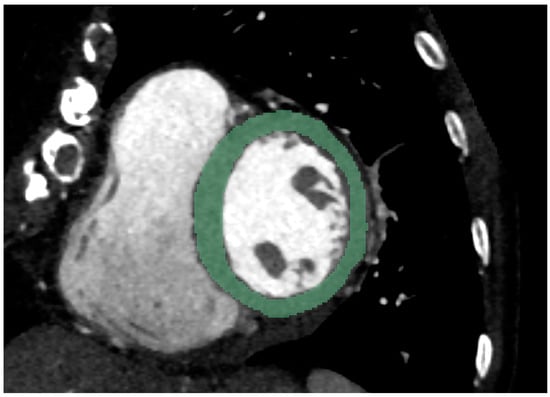

2.2. Chest CT Imaging Analysis

2.3. Radiomics Feature Extraction